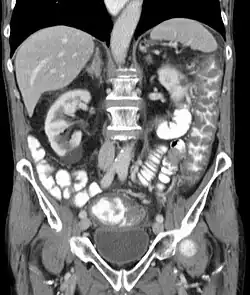

Im Ultraschall und in der Computertomographie kann man die langstreckige Darmwandverdickung des Dickdarmes erkennen. Endoskopisch sieht man im Dickdarm grünliche Fibrinbeläge, die teils fleckig, teils flächenhaft zu finden sind.